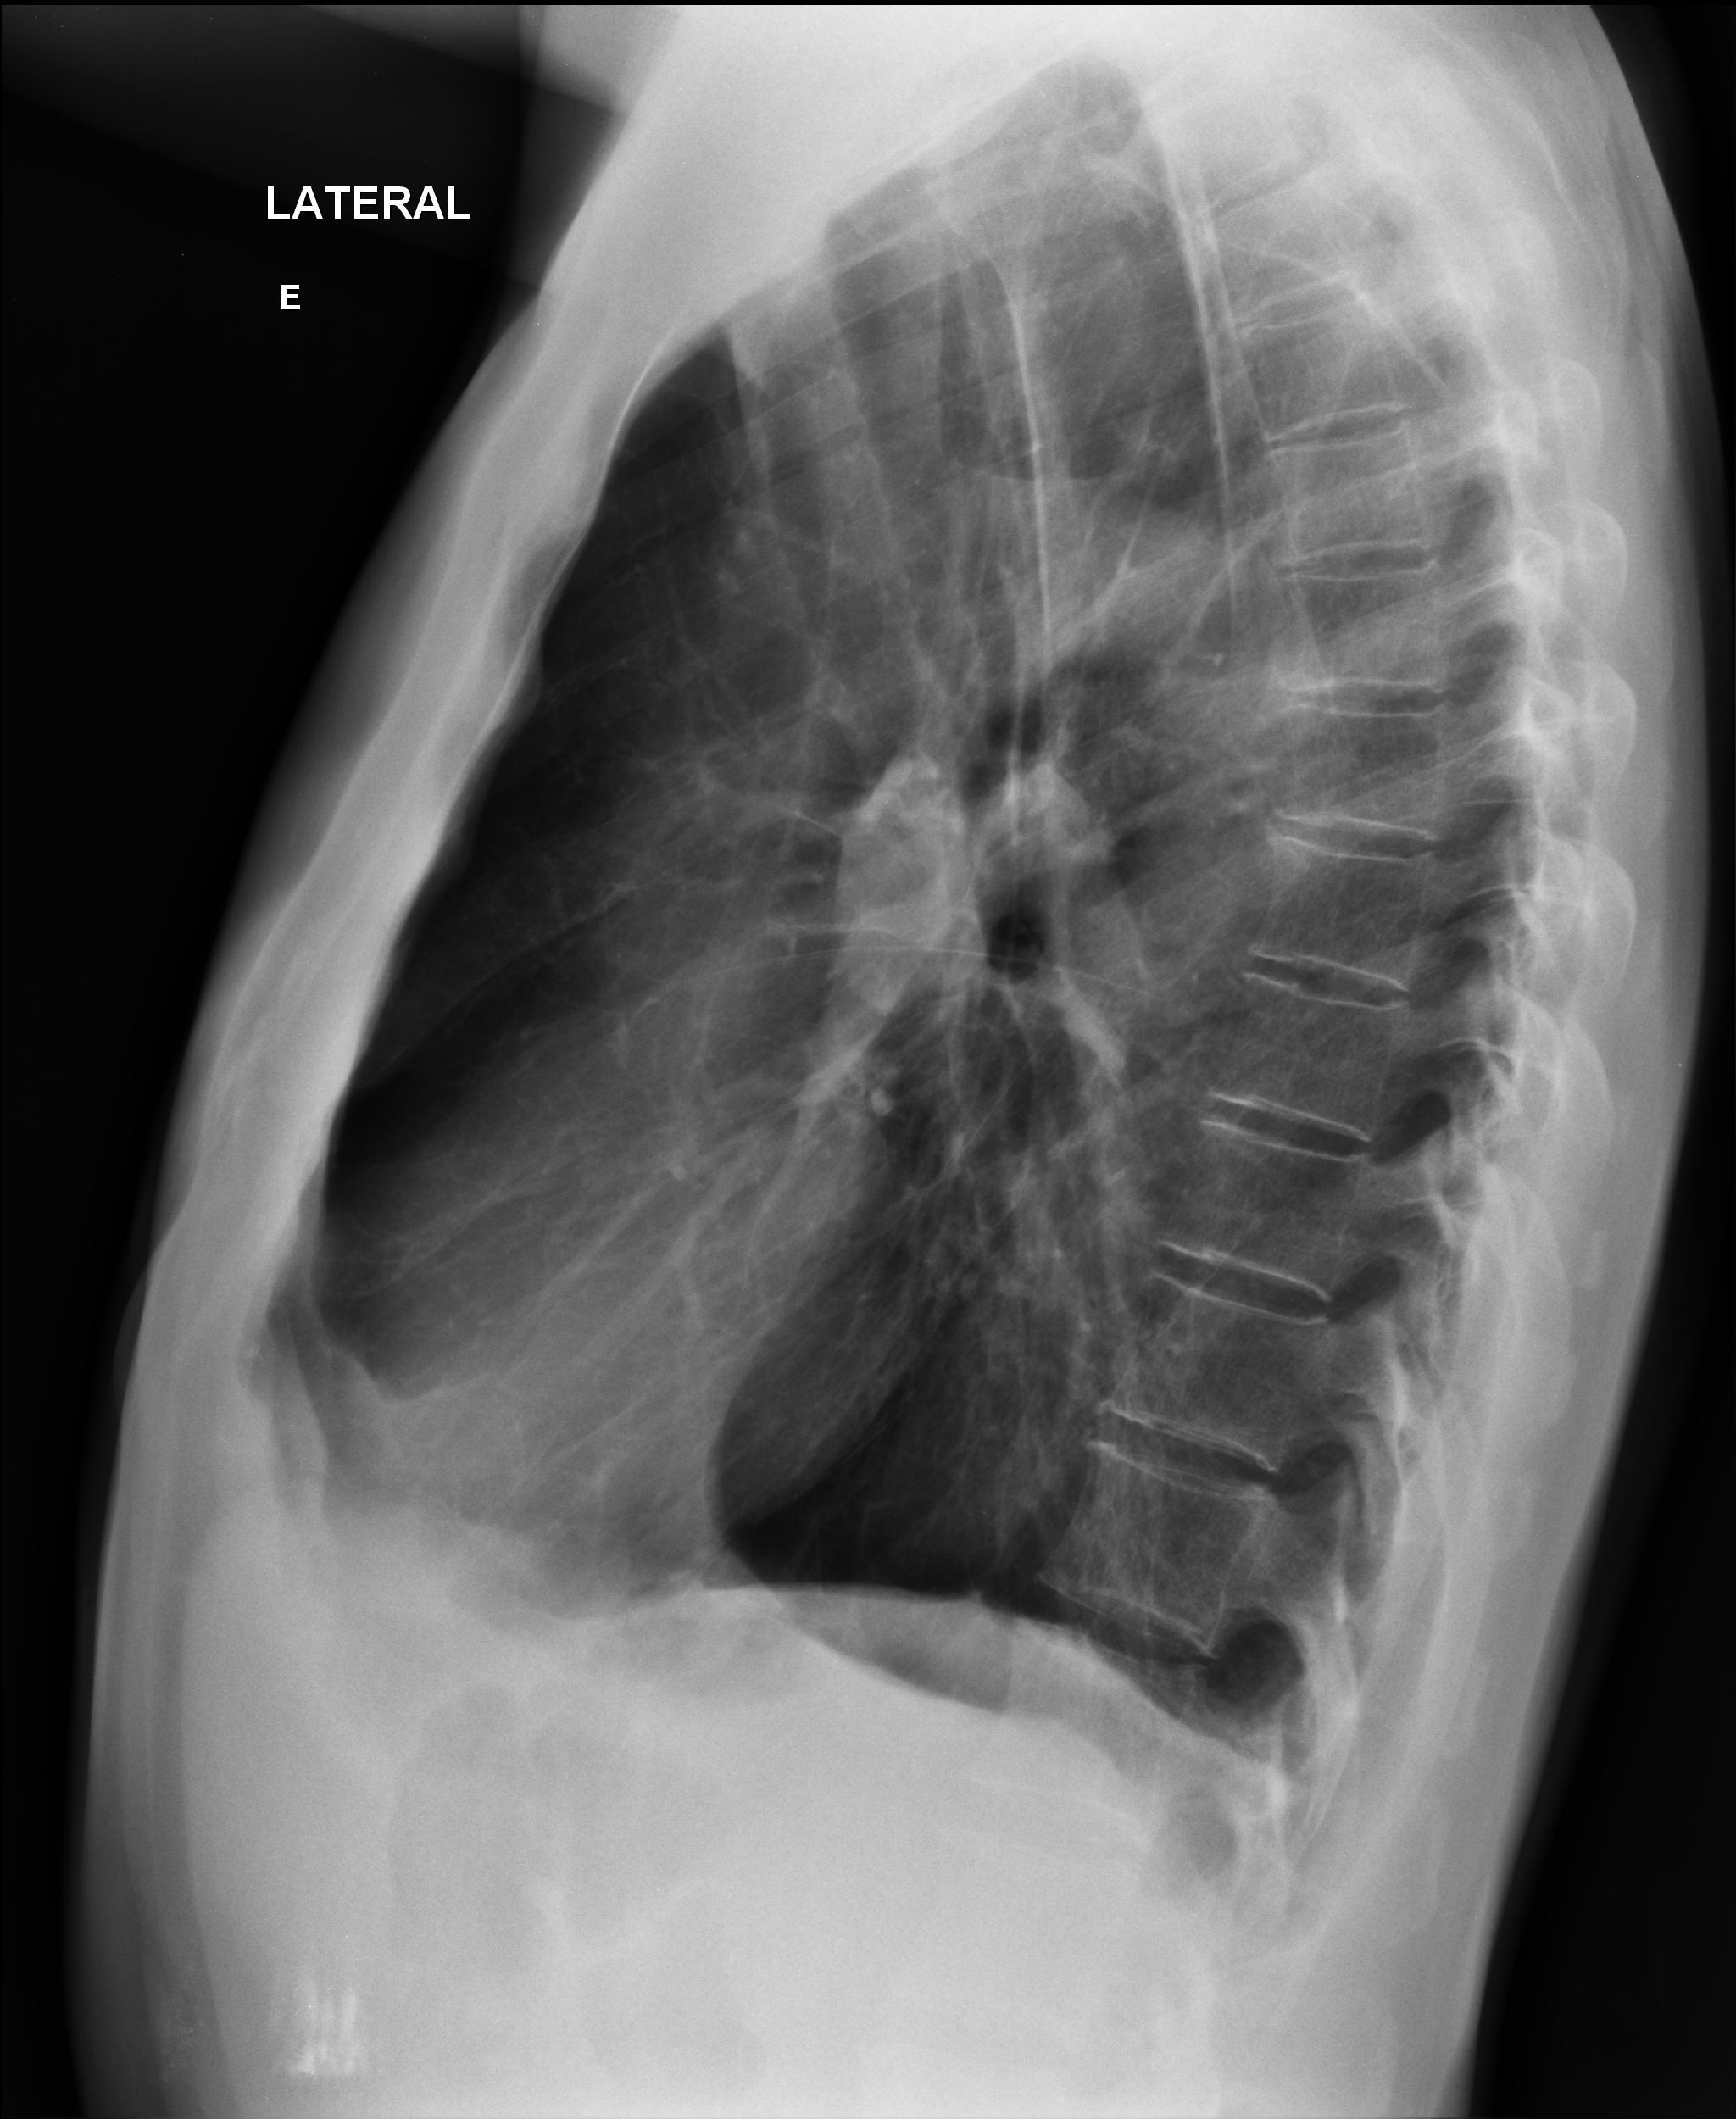

Caso relatado na Reunião de Discussão de Casos Clínicos do Hospital Universitário Prof. Polydoro Ernani de São Thiago, iniciada pelos Profs. Jorge Dias de Matos, Marisa Helena César Coral e Rosemeri Maurici da Silva, em julho de 2017. No dia 14 de junho de 2018, no auditório do HUPEST, realizou-se a apresentação e discussão do caso cujo registro é apresentado a seguir. Trata-se da discussão de onze casos em radiologia torácia, de forma interativa com a plateia, e assim ocorre também neste artigo.